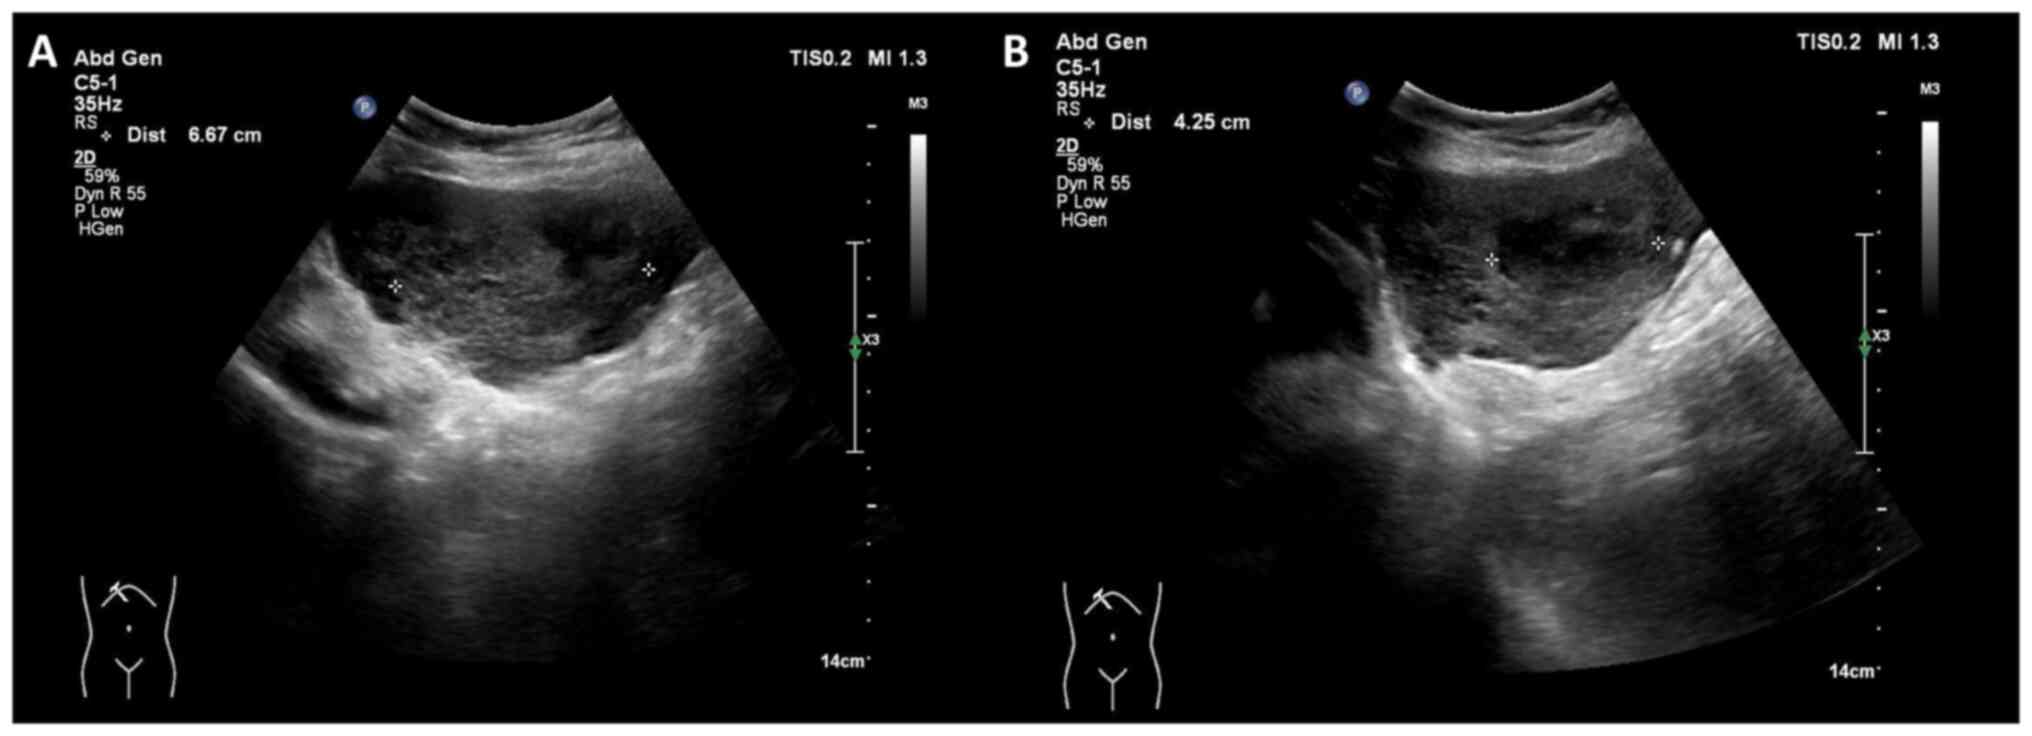

Owing to immunodeficiency and the risk of pancytopenia, chemotherapy was not suggested by the hematologist. Considering the size and location of the hepatic lesions, as well as the patient's overall health and comorbidities, a multidisciplinary team decided to proceed with involved site radiotherapy (ISRT) as the primary modality. Given the bilateral lobe involvement, huge tumor burden and relatively small normal liver volume, a stepped response-adapted approach was planned. A radiation therapy plan of 24 Gy in 16 fractions for the larger tumor was first developed and administered in March 2024 (Fig. 5). Four-dimensional CT (4DCT) was employed during the treatment planning phase to account for respiratory motion. By capturing tumor movement across various respiratory phases, 4DCT enabled the creation of a motion-compensated treatment plan, ensuring precise targeting of hepatic lesions while minimizing the radiation dose to surrounding normal tissues. The larger tumor was irradiated first, with the smaller tumors primarily receiving a scatter dose (mean dose, 447.4 cGy). During the radiotherapy course, significant tumor shrinkage was observed, with the tumor diameter decreasing from 154.9 to 131.4 cm3 and the volume from 6.6 to 5.1 cm3. This prompted the first adaptation of the radiation plan, which involved re-defining the clinical target volume to reflect the reduced tumor size. The updated plan was applied for the last four fractions of radiotherapy, starting from the 13th fraction. The patient tolerated radiotherapy well, with only grade I gastrointestinal upset, graded according to the Common Terminology Criteria for Adverse Events (CTCAE), version 4.0 (8). The patient showed no signs of immunosuppression or the deterioration of pre-existing conditions. Throughout the radiation therapy period, laboratory assessments, including hematological, liver and kidney function tests, demonstrated results within normal limits. Follow-up MRI at 1 month after the first radiotherapy plan showed a marked reduction in both directly irradiated and non-irradiated lesions. For the initial ISRT plan (Fig. 5A), the tumor volumes were 154.9 and 6.6 cm3 for the larger and smaller tumors, respectively. The normal liver volume was 798 cm3. For the response-adapted plan (Fig. 5B), after significant tumor shrinkage, the tumor volumes reduced 38.98 and 2.78 cm3, respectively. The normal liver volume increased to 913.13 cm3. These changes were observed during follow-up imaging, which prompted the response-adapted plan prescribing boost doses of 6 and 8 Gy to the residual lesions in segments 2/4a and 6, respectively (Fig. 5). Consequently, a local radiation boost to the bilateral hepatic lesions was planned, delivering an additional 6 Gy to the segment 2/4a tumor and 8 Gy to the segment 6 tumor in four fractions. At 4 months post-treatment, follow-up MRI (Fig. 6) demonstrated no evidence of residual malignancy. At 7 months post-treatment, whole-body PET revealed no metabolic evidence of malignancy (Deauville criteria score 1) (9) (Fig. 6). No abnormal indicators were observed in the physical, hematological or hepatological examinations at the follow-up evaluations, which were performed every 3 months. This schedule will continue for at least 2 years and may transition to every 6 months based on the patient's condition and physician's assessment. The patient remained healthy and without signs of relapse following radiotherapy.

Figure 5.

Radiation treatment plan for ISRT. (A) The initial ISRT plan shows the 24-Gy isodose line (green) encompassing the larger tumor. The smaller lesion is not covered in this plan, receiving only a scatter dose. The tumor volumes are 154.9 and 6.6 cm3, respectively. The normal liver volume is 798 cm3. (B) The response-adapted plan prescribes boost doses of 6 Gy (aqua) and 8 Gy (green) to the residual lesions in segments 2/4a and 6, respectively. The tumor volumes are 38.98 and 2.78 cm3, respectively. The normal liver volume is 913.13 cm3. ISRT, involved site radiotherapy.

In the present case, response-adapted radiation therapy was used to optimize the dose delivery. Typically, this approach includes assessing the tumor response to an initial radiation course or another treatment modality using imaging or diagnostic tools. Based on this assessment, the radiation plan is adjusted in terms of dose, target area or technique to maximize treatment efficacy while minimizing damage to the surrounding healthy tissues. A similar response-based approach was demonstrated in a phase II trial by Pinnix et al (22), which investigated radiotherapy for orbital indolent B-cell lymphoma, employing a response-adapted ultra-low-dose protocol initiated with a 4-Gy dose, followed by an additional 20 Gy for cases of persistent disease. The trial demonstrated a 2-year local control rate of 89.4%, with 90% of patients achieving a complete response and no grade 3 or higher adverse effects. In the present case, radiation therapy dosages and normal tissue constraints were guided by recommendations provided by the International Lymphoma Radiation Oncology Group (23). Considering the bilateral lobe involvement and limited normal liver volume (798 cm3; compared with the average normal adult liver volume of 1,000-1,400 cm3 in females), the larger tumor was irradiated first, with the smaller tumors primarily receiving a scatter dose (mean dose, 447.4 cGy). Using scatter doses for smaller tumors can be appropriate in certain scenarios, given the highly radiosensitive nature of lymphoma (as low as 4 Gy). Although no significant toxicities were observed during the 7-month follow-up, the potential for late toxicity, such as radiation-induced liver disease (RILD) or central biliary tract toxicity, persists, and this is more common in cases with large liver volume irradiation or central lesions. Toesca et al (24,25) highlighted strategies for predicting and mitigating RILD and central biliary tract toxicity, emphasizing the importance of personalized treatment planning and careful dose management to minimize risks. In the present study, subsequent MRI follow-up indicated a partial response, leading to the administration of additional radiation (6 Gy to the segment 2/4a tumor and 8 Gy to the segment 6 tumor, delivered in four fractions). This approach minimizes radiation exposure to the uninvolved normal liver while ensuring adequate treatment for both tumors. In a previous study, in patients with gastric mucosa-associated lymphoid tissue lymphoma treated with definitive radiotherapy, the median time to achieve complete remission was 3.9 months, with some cases requiring >12 months for confirmation through follow-up biopsies (26). This variability underscores the importance of careful, long-term monitoring to evaluate treatment outcomes and ensure sustained disease control.